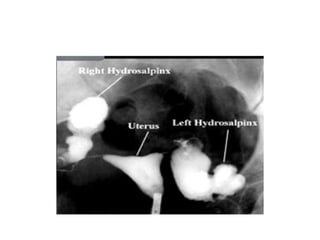

• Hydrosalpinx

• Common cause- salpingitis

• Distal tubal occlusion- dilatation of proximal

segment

• Hydrosalpinx • Commoncause- salpingitis • Distal tubal occlusion- dilatation of proximal segment